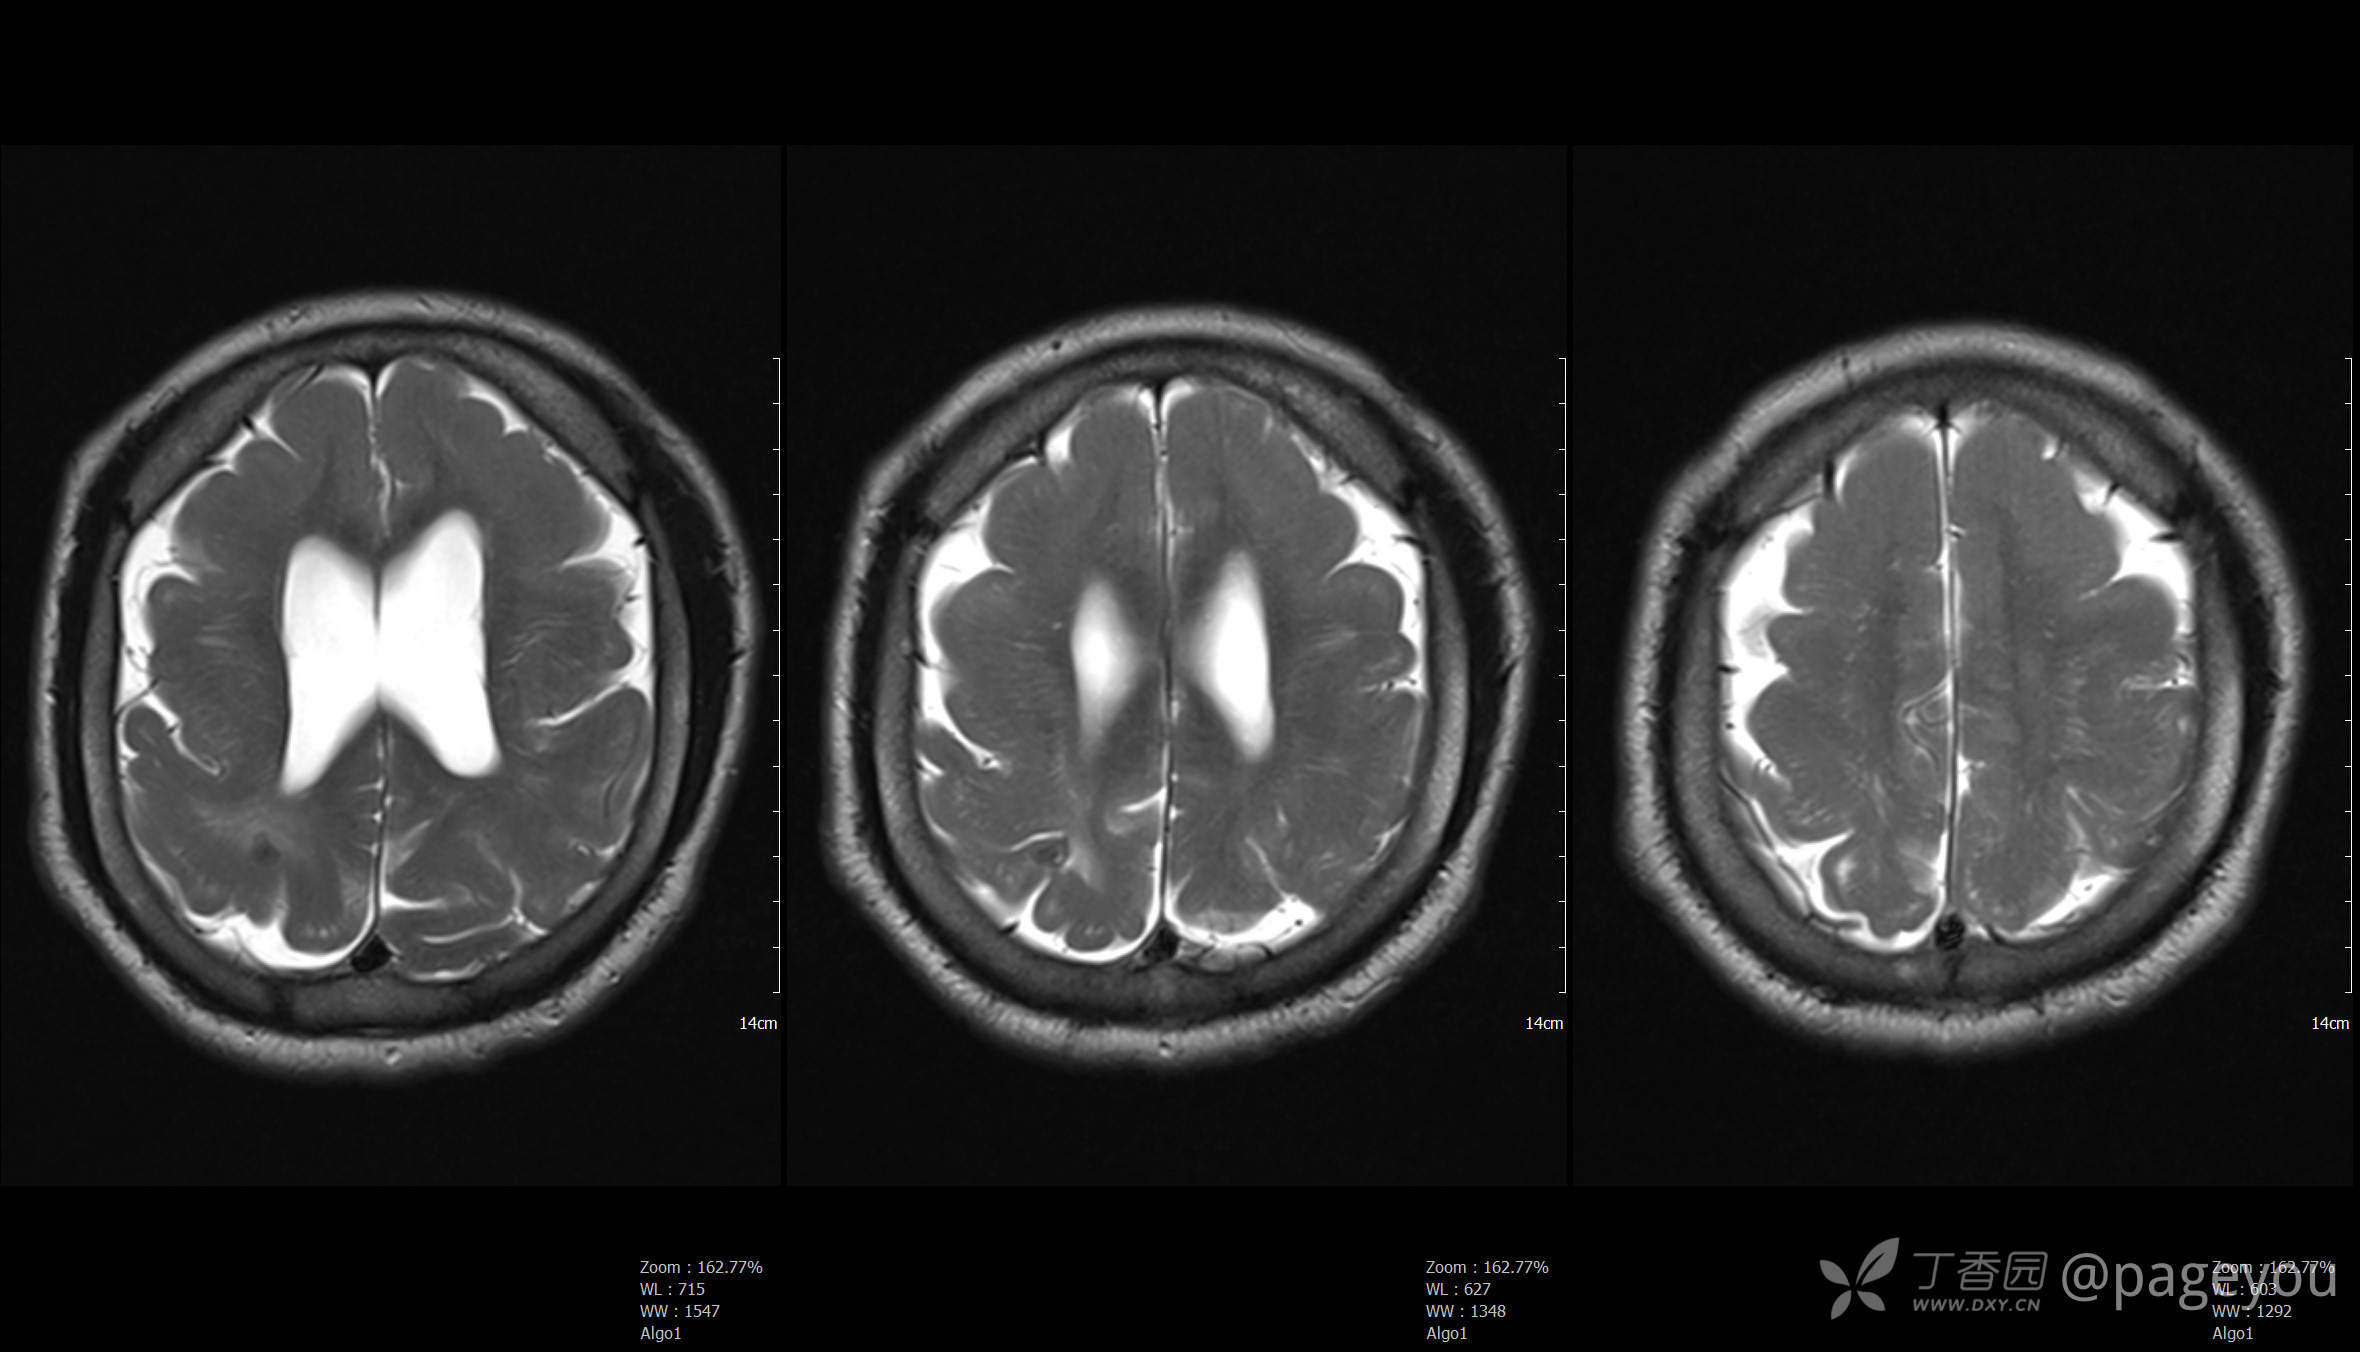

头颅MRI: